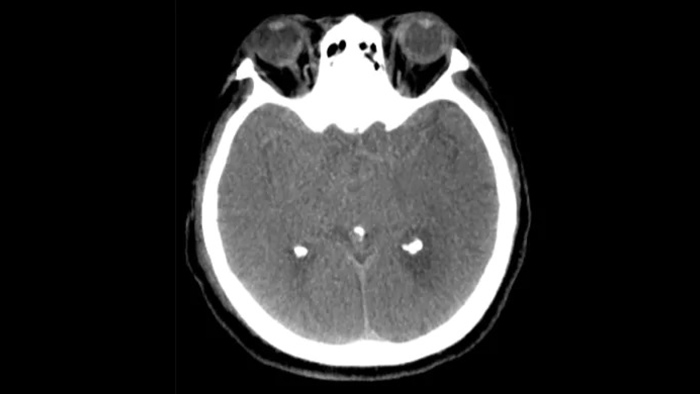

SmartCT Soft Tissue  génère une visualisation des tissus mous de type TDM et prend en charge le diagnostic des AVC de trois façons. Une acquisition sans produit de contraste facilite la détection des changements ischémiques précoces. Une acquisition en phase précoce permet d’identifier l’occlusion proximale. Une acquisition avec agent de contraste en phase tardive prend en charge la détection des collatérales.

Utilisez des images de SmartCT Soft Tissue (type TDM) de la suite neurovasculaire pour vérifier la réussite du traitement et les hémorragies.